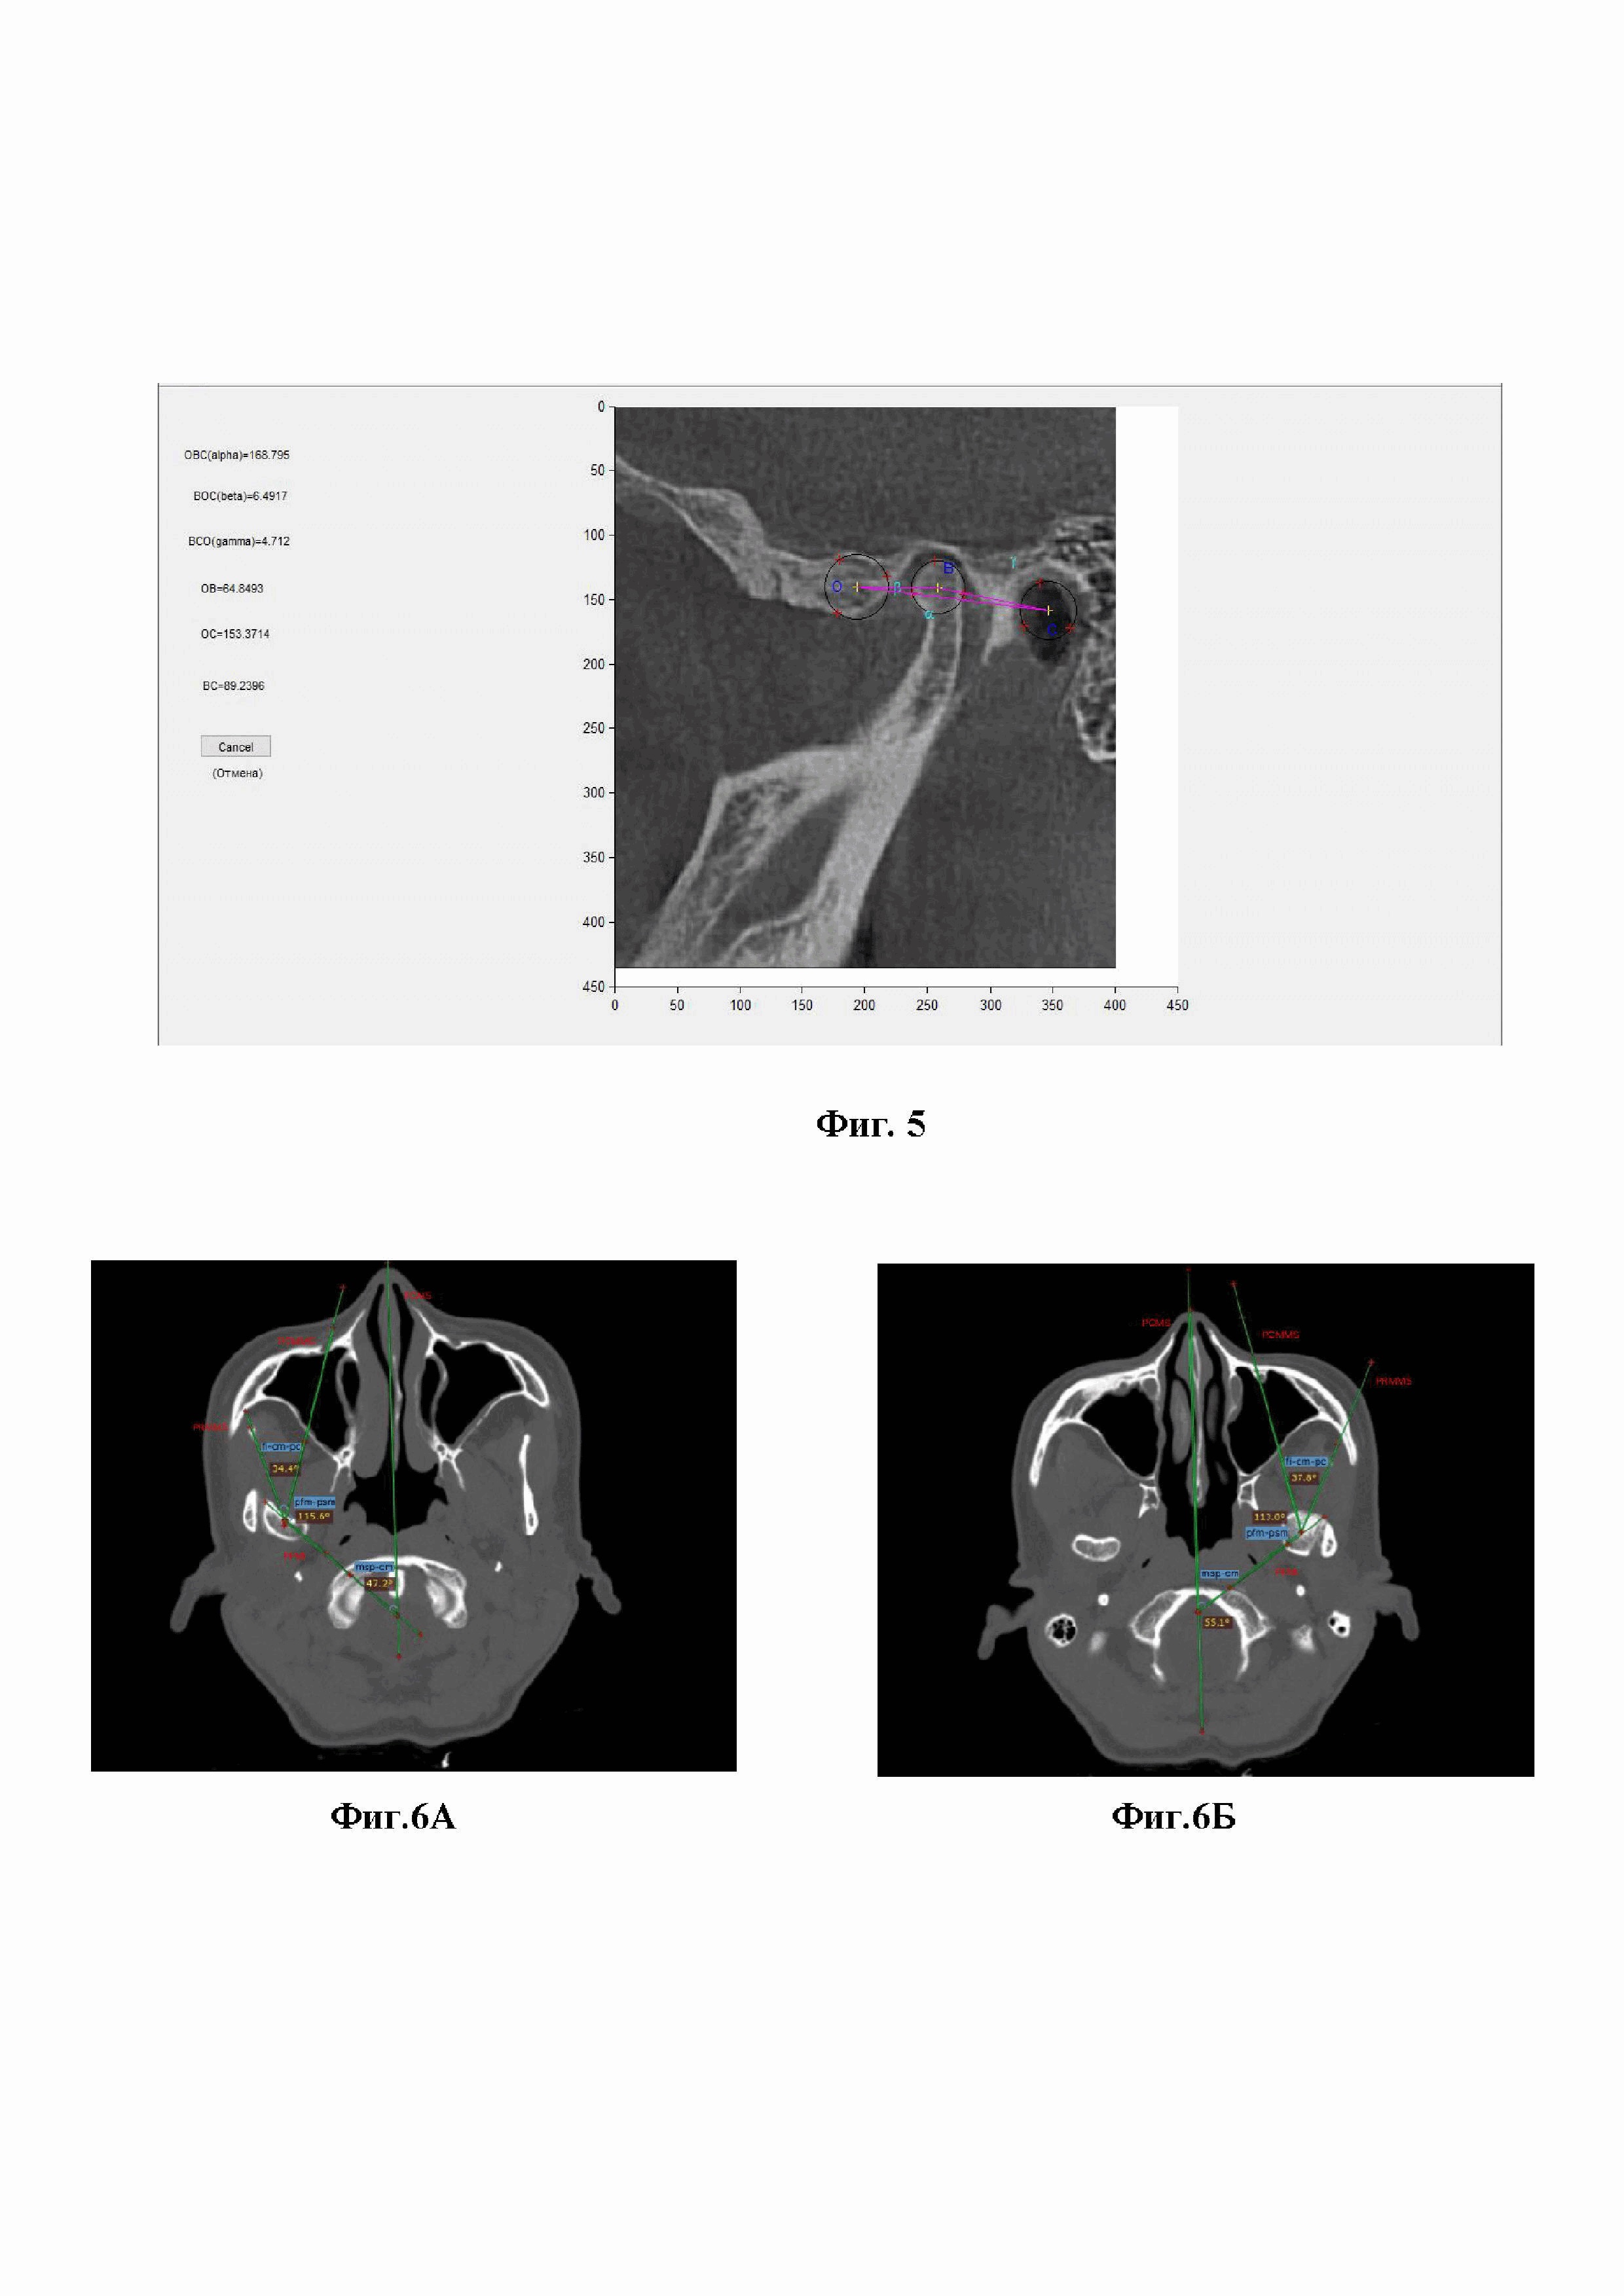

Далее определяем углы, образованные при пересечении срединно-сагиттальных и фронтальных плоскостей (фиг.6).

3.10. Угол msp-cm равен слева 55.1°, справа 47.2°. Данный угол образован срединно-сагиттальной плоскостью черепа и фронтальной плоскостью ГНЧ. Данный угол показывает отношение положения головки нижней челюсти к костям мозгового отдела черепа.

3.11. Угол fi-cm-pc равен слева 37.8°, справа 34.4°. Данный угол образован пересечением срединно-сагиттальных плоскостей ГНЧ и ветви нижней челюсти. Значение этого угла позволяет определить угол отклонения срединно-сагиттальной плоскости ГНЧ от срединно-сагиттальной плоскости ветви нижней челюсти.

3.12. Угол pfm-psm, образованный срединно-сагиттальной и фронтальной плоскостями ГНЧ равен слева 113°, справа 115.6°.

Для определения области наложения пластины необходимо определить физиологичное положение головок нижней челюсти для правильного позиционирования пластины относительно ветви нижней челюсти. Для этого в программе для ЭВМ по 3D-рентгенологическому изображению нижней челюсти в сагиттальной проекции по контору анатомического образования расставляли маркеры, по которым вписывается окружность. После расстановки 9 маркеров по объектам сравнения строится треугольник, с вершинами в центрах окружностей, с выявляемыми и подписанными углами (фиг. 7). Угол альфа - показатель дистализации головки в межбугорковом положении зубных рядов, он равен 25.5278°. Угол бетта-показатель положения головки относительно суставного бугорка, он равен 129.8683°.